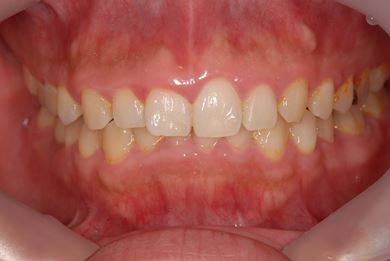

インプラントの症例写真 IMPLANT

抜歯即日スピードインプラント治療

| 性別/年齢 | 男性 / 38歳 | ||||||||||||||||||||||||||||||||

| 主訴 | 10年位前に虫歯治療をした右下奥歯のつめ物が取れ、再治療を受けた際にインプラントをすすめられたため、治療相談で来院。 | ||||||||||||||||||||||||||||||||

| 治療方針 | 抜歯と同時にインプラントを埋入し、治療期間を短縮する。 | ||||||||||||||||||||||||||||||||

| 治療内容 | インプラント1本(抜歯即日スピードインプラント)、ハイブリッドセラミッククラウン1本 | ||||||||||||||||||||||||||||||||

| 総治療費 | 257,250円 | ||||||||||||||||||||||||||||||||

| 治療期間 | 6ヶ月 |